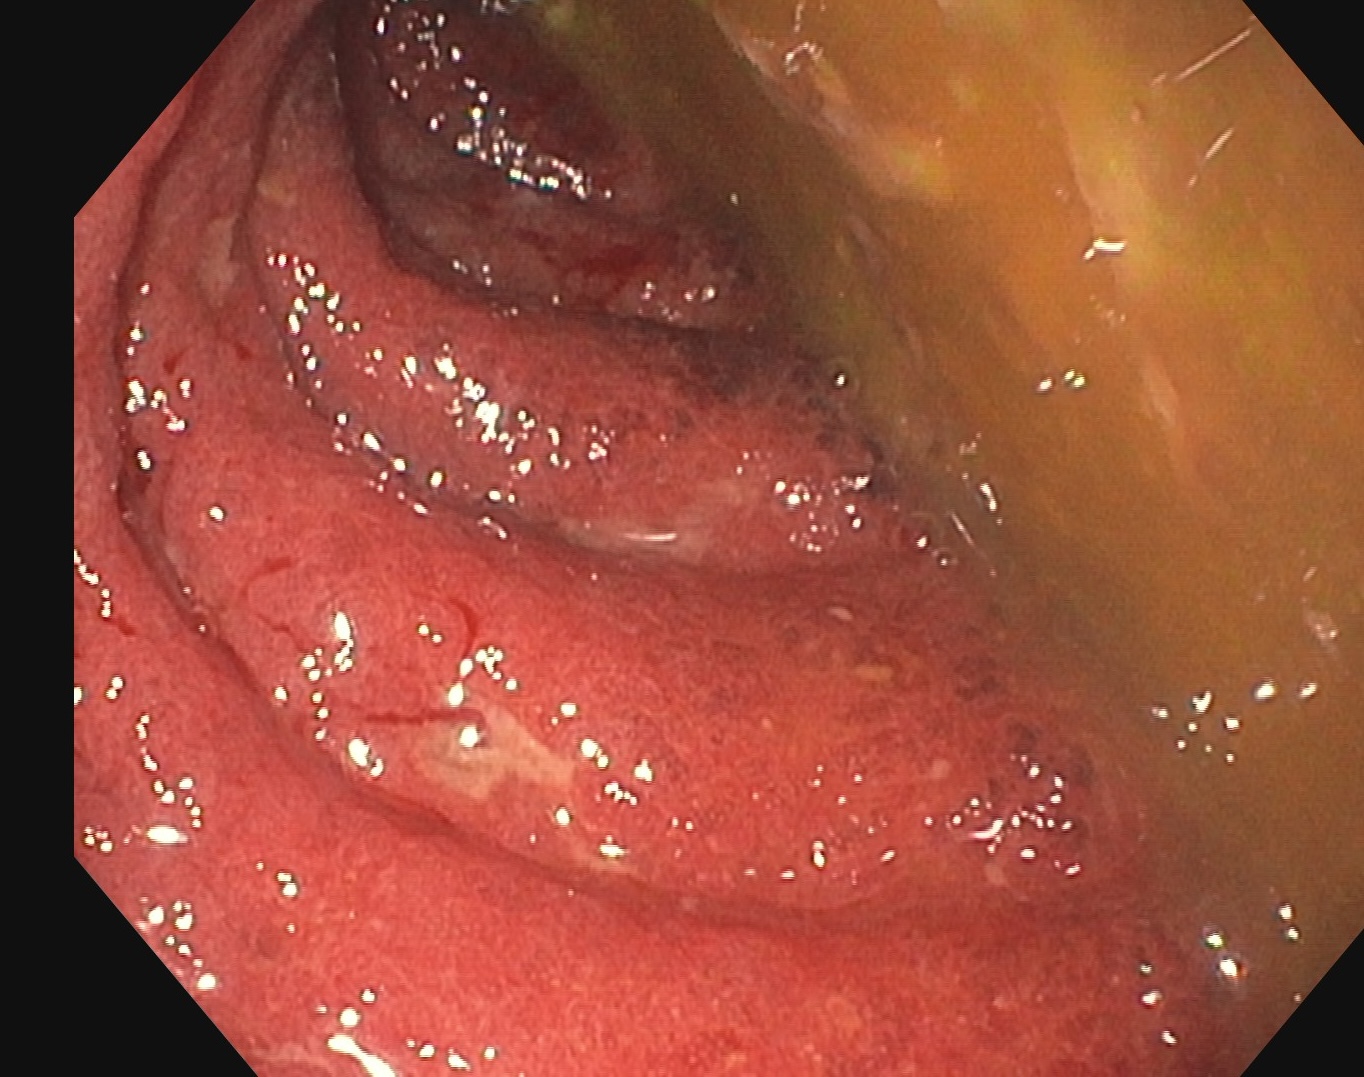

Endoscopie Mayo 3 UCESI 7/8 ulcères creusants

L’histologie confirme une RCH grave sans surinfection par le CMV.

Les images échographiques correspondent parfaitement aux images endoscopiques, et sont finalement beaucoup plus précises que les images scanographiques.